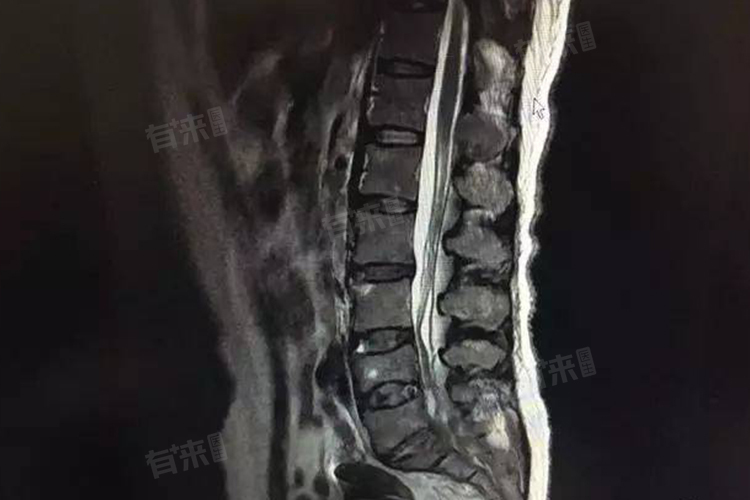

- 乳腺癌骨转移的诊断主要依赖于影像学检查和病理学检查。常用的影像学检查方法包括X光、CT、PET-CT、核磁共振等,这些检查可以明确显示骨转移的部位、范围和程度。